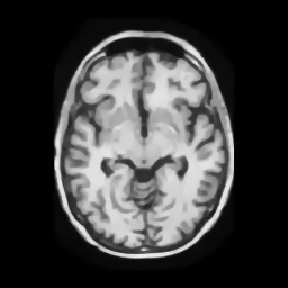

Reconstructing under-sampled k-space measurements in Compressed Sensing MRI (CS-MRI) is classically solved with regularized least-squares. Recently, deep learning has been used to amortize this optimization by training reconstruction networks on a dataset of under-sampled measurements. Here, a crucial design choice is the regularization function(s) and corresponding weight(s). In this paper, we explore a novel strategy of using a hypernetwork to generate the parameters of a separate reconstruction network as a function of the regularization weight(s), resulting in a regularization-agnostic reconstruction model. At test time, for a given under-sampled image, our model can rapidly compute reconstructions with different amounts of regularization. We analyze the variability of these reconstructions, especially in situations when the overall quality is similar. Finally, we propose and empirically demonstrate an efficient and data-driven way of maximizing reconstruction performance given limited hypernetwork capacity. Our code is publicly available at https://github.com/alanqrwang/RegAgnosticCSMRI.